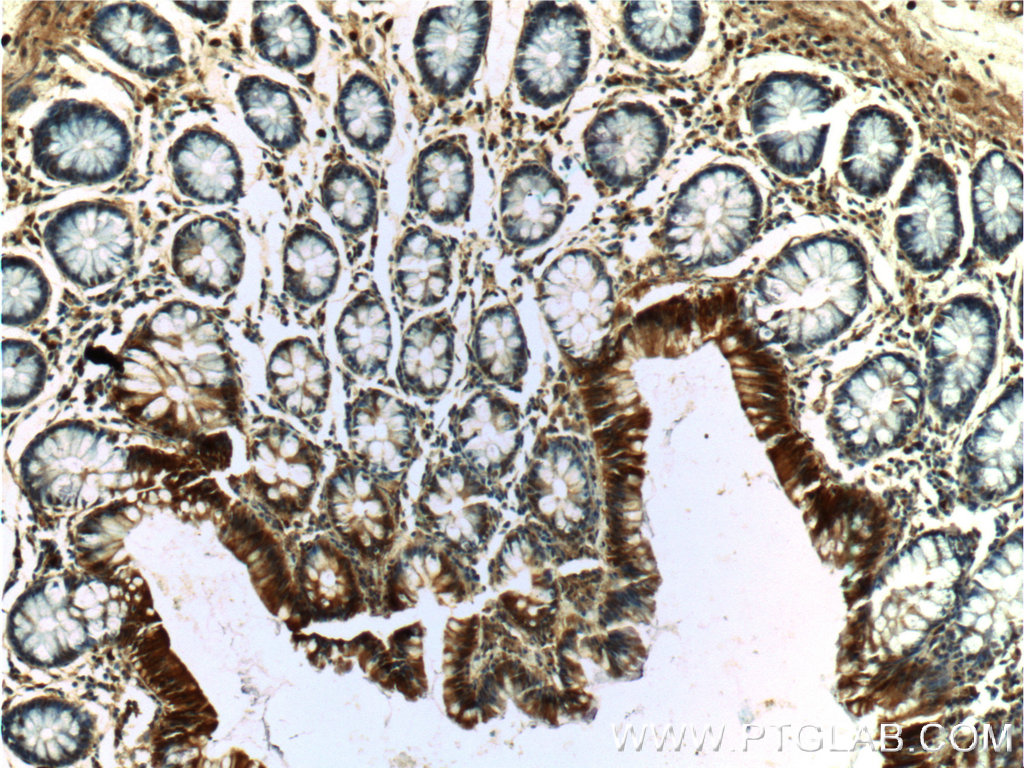

| Positive IHC detected in | human breast cancer tissue,  human colon tissue Note: suggested antigen retrieval with TE buffer pH 9.0; (*) Alternatively, antigen retrieval may be performed with citrate buffer pH 6.0  |

| Immunohistochemistry (IHC) | IHC : 1:50-1:200 |